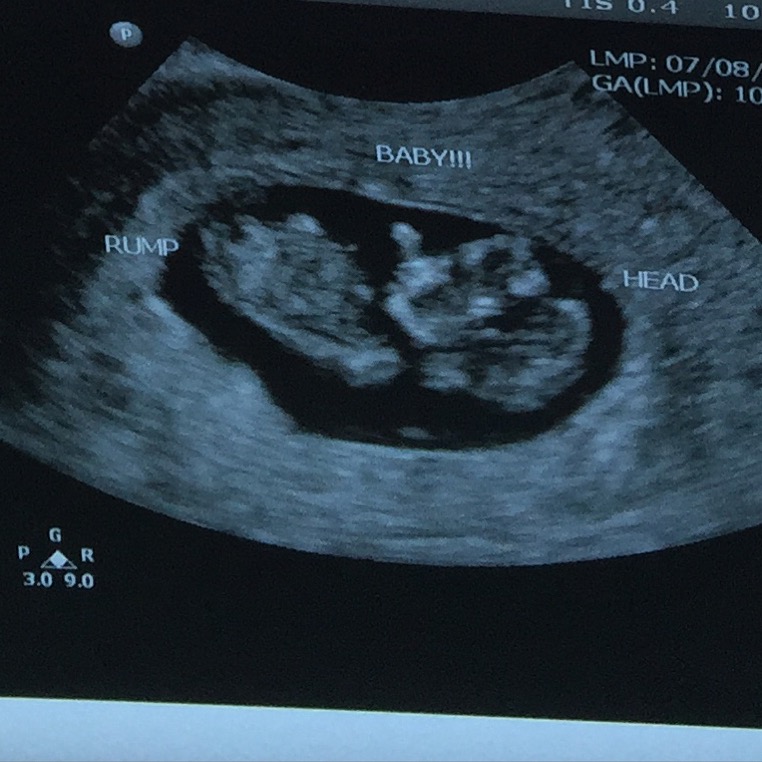

The nub theory can help you discover your baby's gender at the 12 week scan, all you need is your first ultrasound picture. How To Know Baby Boy Or Girl In Ultrasound Report Part A Aqsa Mehmood Youtube

Still, the results of your . After 18 weeks of pregnancy and beyond, carr said that ultrasounds have pretty good reliability for gender prediction if the baby is in a good . The nub theory can help you discover your baby's gender at the 12 week scan, all you need is your first ultrasound picture. "with a female baby this can appear to look like three white lines. The accuracy can vary from 70.3% at 11 . One recent study found that the ultrasound technician correctly predicted a baby's gender 98 percent of the time. An early second trimester sonographic indicator of fetal gender. The accuracy of determining your baby's gender increases with how far along you are in the pregnancy.